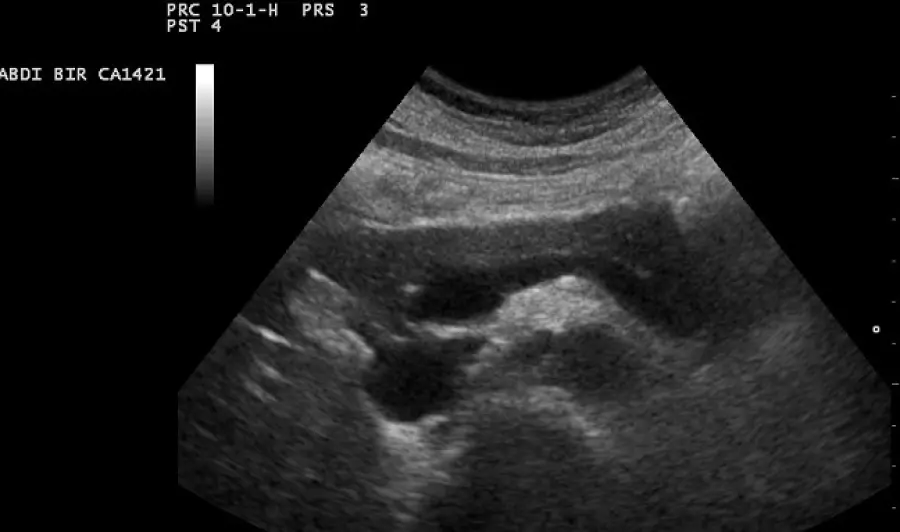

Tra le varie neoplasie, il tumore del pancreas è una patologia in forte crescita in tutto il mondo e tra pochi anni si stima che rappresenterà la seconda causa di morte per cancro in Europa: si contano in Italia circa 13.500 diagnosi in un anno. Per di più il tumore al pancreas è uno dei più aggressivi: solo il 7% degli uomini e il 9% delle donne sopravvivono a 5 anni. Il primo problema è la diagnosi: a tutt’oggi non esiste un metodo per capire precocemente se si è malati di questo carcinoma, perché è asintomatico. Appena il 7% dei casi viene diagnosticato nello stadio iniziale. Sintomi più chiari (variabili a seconda della zona del pancreas dove ha avuto inizio il tumore) compaiono quando il tumore ha iniziato a diffondersi agli organi vicini o ha bloccato i dotti biliari. Possono così manifestarsi perdita di peso e di appetito, ittero (colorazione gialla della pelle), dolore nella parte superiore dell'addome o nella schiena, debolezza, nausea o vomito. Infine, una percentuale di malati che va dal dieci al venti per cento può essere anche colpita da diabete, dovuto all'incapacità delle cellule malate di produrre insulina. Tumore del pancrea nuova tecnica per curare neoplasia inoperabile Una piccola percentuale di malati di tumore del pancreas viene identificata quando il tumore è ancora localizzato e viene dunque sottoposta a un'asportazione chirurgica che ha qualche probabilità di successo, anche se l'intervento è complicato e gravato da molti rischi. In generale le operazioni, molto impegnative, sono associate a una mortalità  che può arrivare al 10% e comunque non sono sempre possibili, dato che la malattia si diffonde con rapidità. Dopo l'intervento può essere inoltre necessario eseguire una chemioterapia, che rappresenta anche l'unica arma a disposizione, insieme alla radioterapia, per i tumori che non sono operabili. Per fortuna la scienza sta facendo passi da gigante, e le eccellenze italiane continuano a distinguersi per i loro primati e innovazioni. Nei giorni scorsi, ad esempio, all’ospedale di Terni l’equipe di Epatologia e Gastroenterologia, diretta da Mariano Quartini, ha effettuato per la prima volta in Umbria un trattamento di ablazione cioè distruzione non chirurgica per via percutanea con guida ecografica di un tumore del pancreas giudicato inoperabile per infiltrazione vascolare e che non aveva risposto alla terapia oncologica convenzionale. La procedura, denominata IRE, è stata eseguita in anestesia generale senza complicanze e il paziente, un ottantenne di fuori regione, è stato dimesso dopo 48 ore dall’intervento. Il sistema usato è stato quello dell’Elettroporazione Irreversibile (IRE), un’ablazione non termica di formazioni tumorali, che attraverso impulsi elettrici della durata di alcuni microsecondi, tramite l’utilizzazione di più aghi, in questo caso 5, altera in modo permanente le membrane delle cellule, causandone la morte. Questo metodo, non comportando aumento della temperatura dell’area trattata, non danneggia le strutture termosensibili come i dotti biliari, i vasi arteriosi e venosi e gli organi contigui come lo stomaco. “I trattamenti ablativi percutanei per il tumore del pancreas vengono effettuati in pochi centri italiani – spiega il dottor Mariano Quartini – e con guida ecografica siamo stati i primi ad utilizzare il sistema IRE a livello nazionale. Grazie alla collaborazione con la Radiologia Interventistica, sempre in casi selezionati di tumori del pancreas inoperabili e non rispondenti alla terapia oncologica convenzionale, siamo in grado di utilizzare questa procedura anche sotto guida TAC, così da mettere a disposizione il trattamento ai pazienti che potrebbero trarne giovamento compresi quelli per i quali non fosse praticabile la guida ecografica”. Una nuova speranza, quindi, soprattutto per coloro che non rispondono ai trattamenti tradizionali e per coloro che hanno una neoplasia purtroppo scoperta in fase avanzata e quindi giudicata inoperabile.